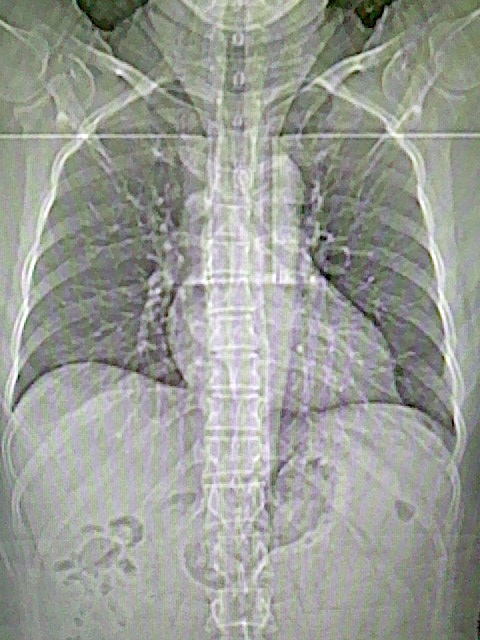

女,52岁,咳嗽,咳痰多日

左下肺陈旧纤维索条!

左肺舌段炎性改变

我见过几例,为炎症后纤维条索

慢性炎症后改变

考虑慢性炎性病灶粘连牵拉改变。

左肺舌叶纤维锁条病变。

左肺上叶下舌段炎症并局部胸膜反应。

左肺舌叶纤维索条影。

左肺舌叶段陈旧性病变

左肺舌段炎性反应。片子的质量太不好了。

左肺舌段炎性

炎性改变

左肺舌叶纤维索条影